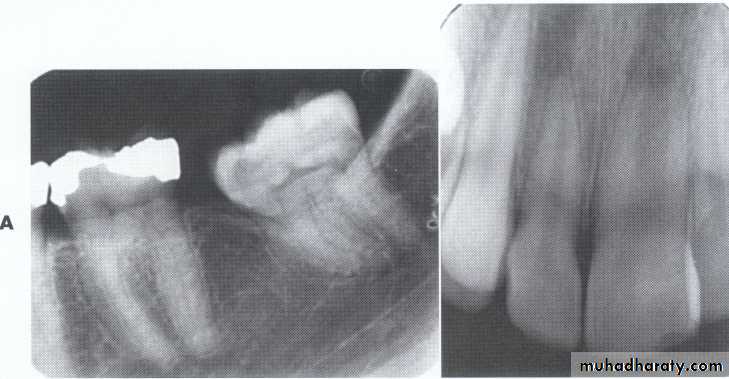

Dilaceration

*Dilaceration is a disturbance in tooth formation that produces a sharp bend or curve in the tooth (root or crown).

*CAUSES: trauma to the calcified portion of a partially formed tooth, or due to true developmental anomaly.

Dilaceration of the crown

specimenX-Ray

Dilacerated root. The apical portion of the root is bent buccally or lingually into the plane of the central ray. Note the halo in the apical region, produced by the PDL

space (arrow).